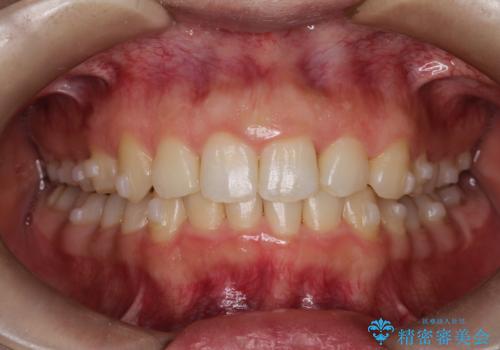

強い叢生がありましたが、抜歯は行わず上下顎ともに、主に歯列弓の拡大を行い叢生を改善しました。

矯正装置としてはマウスピースを使用しています。

見た目、嚙み合わせ及び、治療期間や施術内容に大変ご満足いただきました。